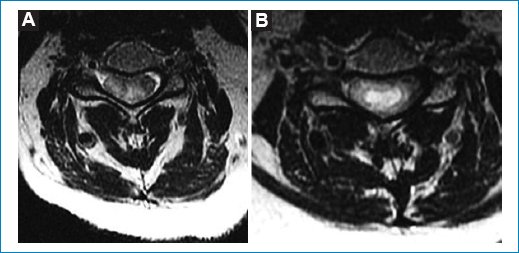

Figura 2. Secuencia axial ponderada en T2. Masa heterogénea. (A) Polo superior. (B) Centro donde predomina el componente quístico.

Figura 5. (A y B) Secuencia axial en dos niveles ponderada para T1. (B y C) Secuencia axial STIR en dos niveles después de administrar contraste endovenoso. Tras la administración de gadolinio, en secuencia STIR se observa realce periférico en anillo, compatible con heterogeneidad tumoral.